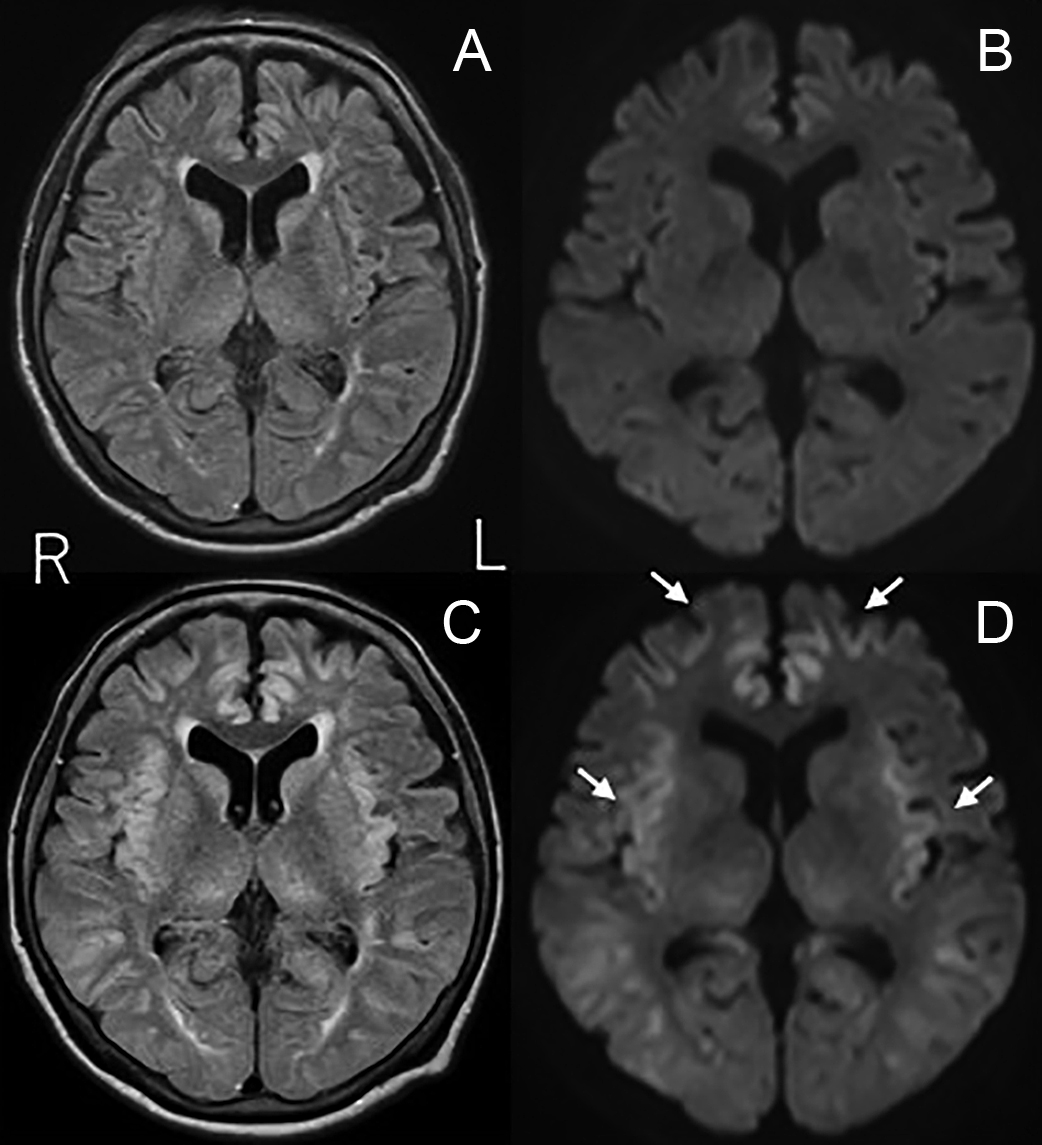

脊髄MRIや髄液検査で異常を認めなかった抗myelin-oligodendrocyte glycoprotein(MOG)抗体関連疾患の1例

A case of anti-myelin-oligodendrocyte glycoprotein (MOG) antibody-associated disease without abnormal findings on spinal MRI and cerebrospinal fluid examination

若月 里江, 武内 智康, 岡 耕太, 竹ノ内 晃之, 渡邊 一樹, 中村 友彦

Rie Wakatsuki, Tomoyasu Bunai, Kouta Oka, Akiyuki Takenouchi, Kazuki Watanabe, Tomohiko Nakamura

2026/03/11